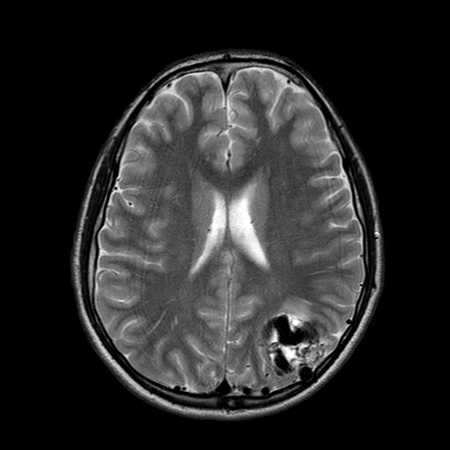

Unruptured left parieto-occipital arteriovenous malformation (axial T2-weighted magnetic resonance imaging scan)

From the collection of Mr R. J. Edwards; used with permission